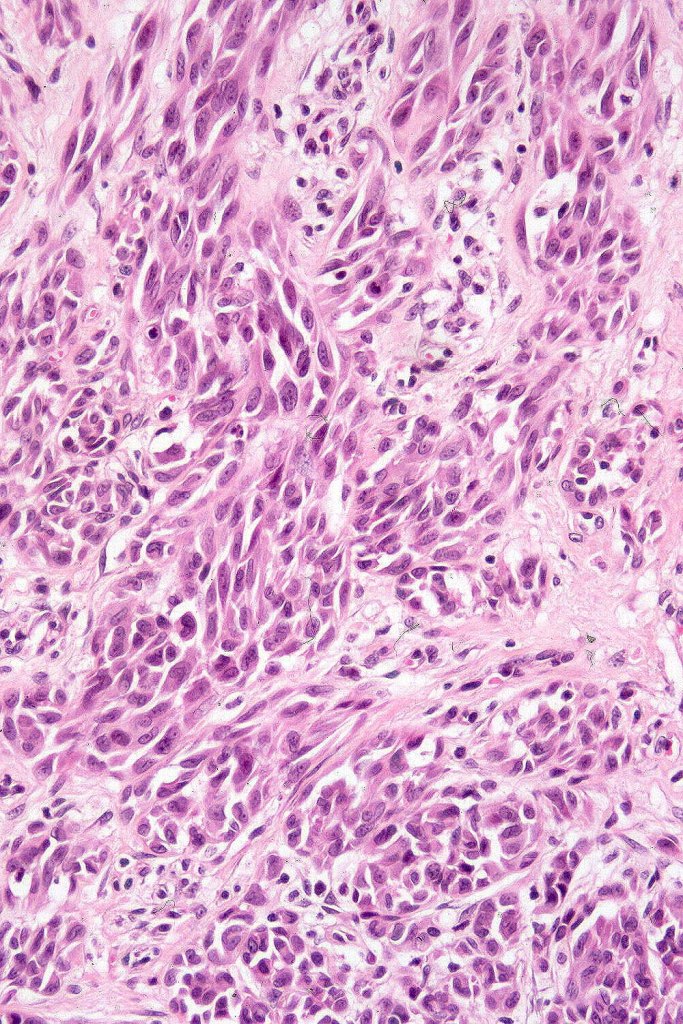

•Spindle, epithelioid and mixed cell variants

•Junctional nests often vertically orientated, dyscohesive with a surrounding retraction artifact

•Pleomorphism is almost invariable but affects all of the population to the same extent i.e., the cells & nuclei all look very much the same

•Spindle cell nests often display a “raining down” growth pattern

•Spindle cells have abundant cytoplasm and vesicular nuclei with small nucleoli

•Epithelioid cell variants often show greater pleomorphism and cells can frequently appear bizarre with abundant, sometimes ground glass cytoplasm and large vesicular nuclei with prominent eosinophilic nucleoli, multinucleate cells are often seen

•Intracytoplasmic pseudoinclusions commonly present in epithelioid cells